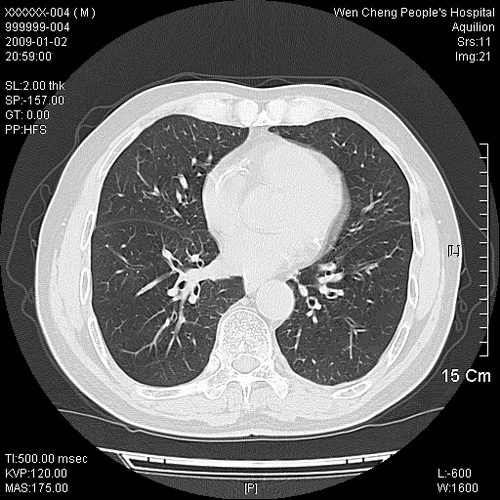

男性,73岁,有慢支病史,肿瘤系列标志物检验正常,血沉及血常规正常

右肺下叶背段小片状 磨玻璃样模糊影,内见血管及含气支气管像,支气管管壁增厚。考虑:慢性炎症!

右肺下叶背段小片状 实性与磨玻璃样影,内见血管及含气支气管像,支气管管壁增厚,边缘见长毛刺影。考虑:慢性炎症或肿瘤!建议抗炎治疗复查,密切观察随访!

右肺下叶片团状影内见扩张的含气支气管和支气管管壁增厚,其周有磨玻璃样模糊影和长毛刺。考虑慢性炎症可能性大。

2、右肺下叶片团状影内见扩张的含气支气管和支气管管壁增厚,其周有磨玻璃样模糊影和长毛刺。考虑周围型肺ca可能,结核不排。

高度提示细支气管肺泡癌,建议抗炎治疗半月观察病灶变化,如无明显改变,建议立即手术治疗.

病变形态非常不好呀,临床上血常规及症状也不明显,不太支持炎性病灶,高度警惕肿瘤病变,最好做个纤支镜检查。